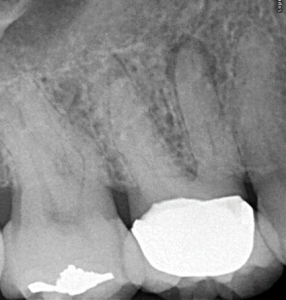

Root Canal / Retreatment

Apical Microsurgery / Apicectomy

Clinical Cases